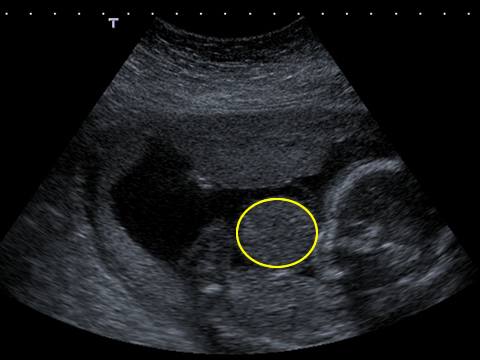

A long axis scan through the fetus shows the herniated liver coming from the anterior abdominal wall of the fetus. The fetal limbs, abdomen and head can also be seen.